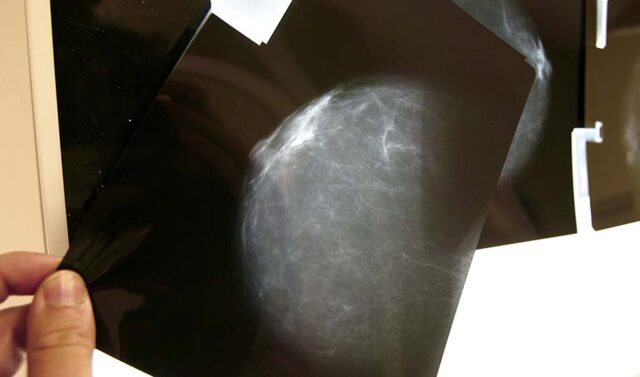

El Servicio Andaluz de Salud (SAS) ha comenzado a llamar a todas las mujeres que tienen resultados no concluyentes en el programa de cribado de cáncer de mama. Este programa está diseñado para brindar atención adecuada y seguimiento a aquellas pacientes con lesiones que, aunque no son consideradas graves, requieren un control médico.

El SAS identificó tres posibles diagnósticos tras una mamografía: negativo, positivo o posiblemente benigno. Las pacientes con resultados negativos o positivos son contactadas apropiadamente. Sin embargo, aquellas con lesiones benignas a veces no recibían la información que necesitaban respecto a seguimientos y futuros exámenes.